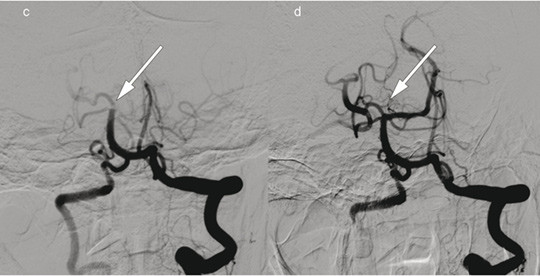

Pasient 2. En kvinne i 70-årene fikk etter hjertekirurgi akutt oppståtte høyresidige lammelser, svimmelhet og dysartri. NIHSS-skåren var 23 poeng (alvorlig hjerneinfarkt). Intravenøs trombolytisk behandling var kontraindisert. Bildet til høyre viser cerebral angiografi med kontrastinjeksjon i venstre a. vertebralis, c) før og d) etter embolektomi av stor trombe (piler) med okklusjon av a. cerebelli superior, a. cerebri posterior og basilaristoppen. Embolektomi ble utført med rekanalisering 220 minutter etter ictus. Hendelsen oppsto antakelig etter hjertekirurgien. Utredning påviste også atrieflimmer. Pasienten fikk antikoagulasjonsbehandling med warfarin, og ved kontroll etter tre måneder var NIHSS-skåren 0 poeng.